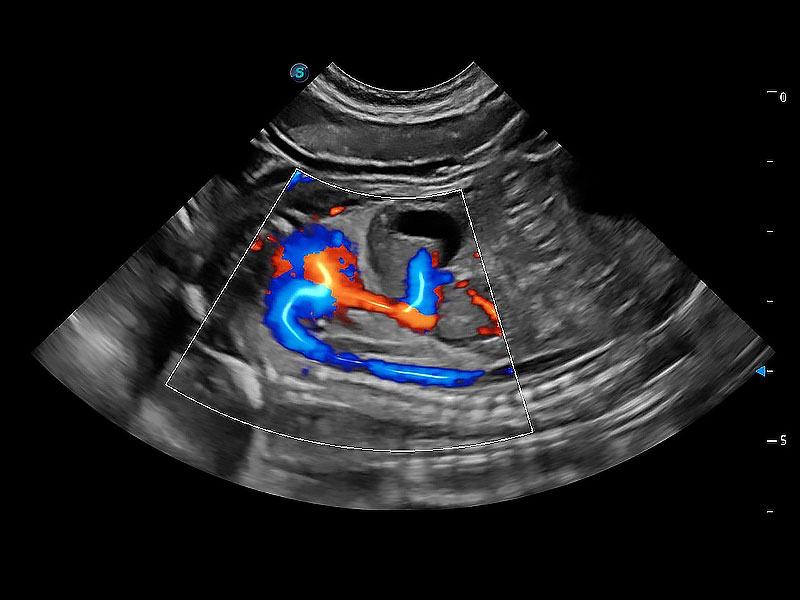

在传统二维血流成像的基础上,呈现血流的立体感,具有动感的生命力之美。即便是微小的血管也能轻松应对,提高了血流的视觉敏感性。

实时用颜色表示心肌组织运动,观察和定量组织的运动情況,对快速检测与评估心肌的灌注和活性、电传导及心肌收缩和舒张功能等均能提供重要的诊断信息。

通过360度任意调节3条M型取样线,在同一心动周期上观察心脏不同位置的运动曲线,得到准确的心功能测量数据,有效评估心肌运动及左心室功能。